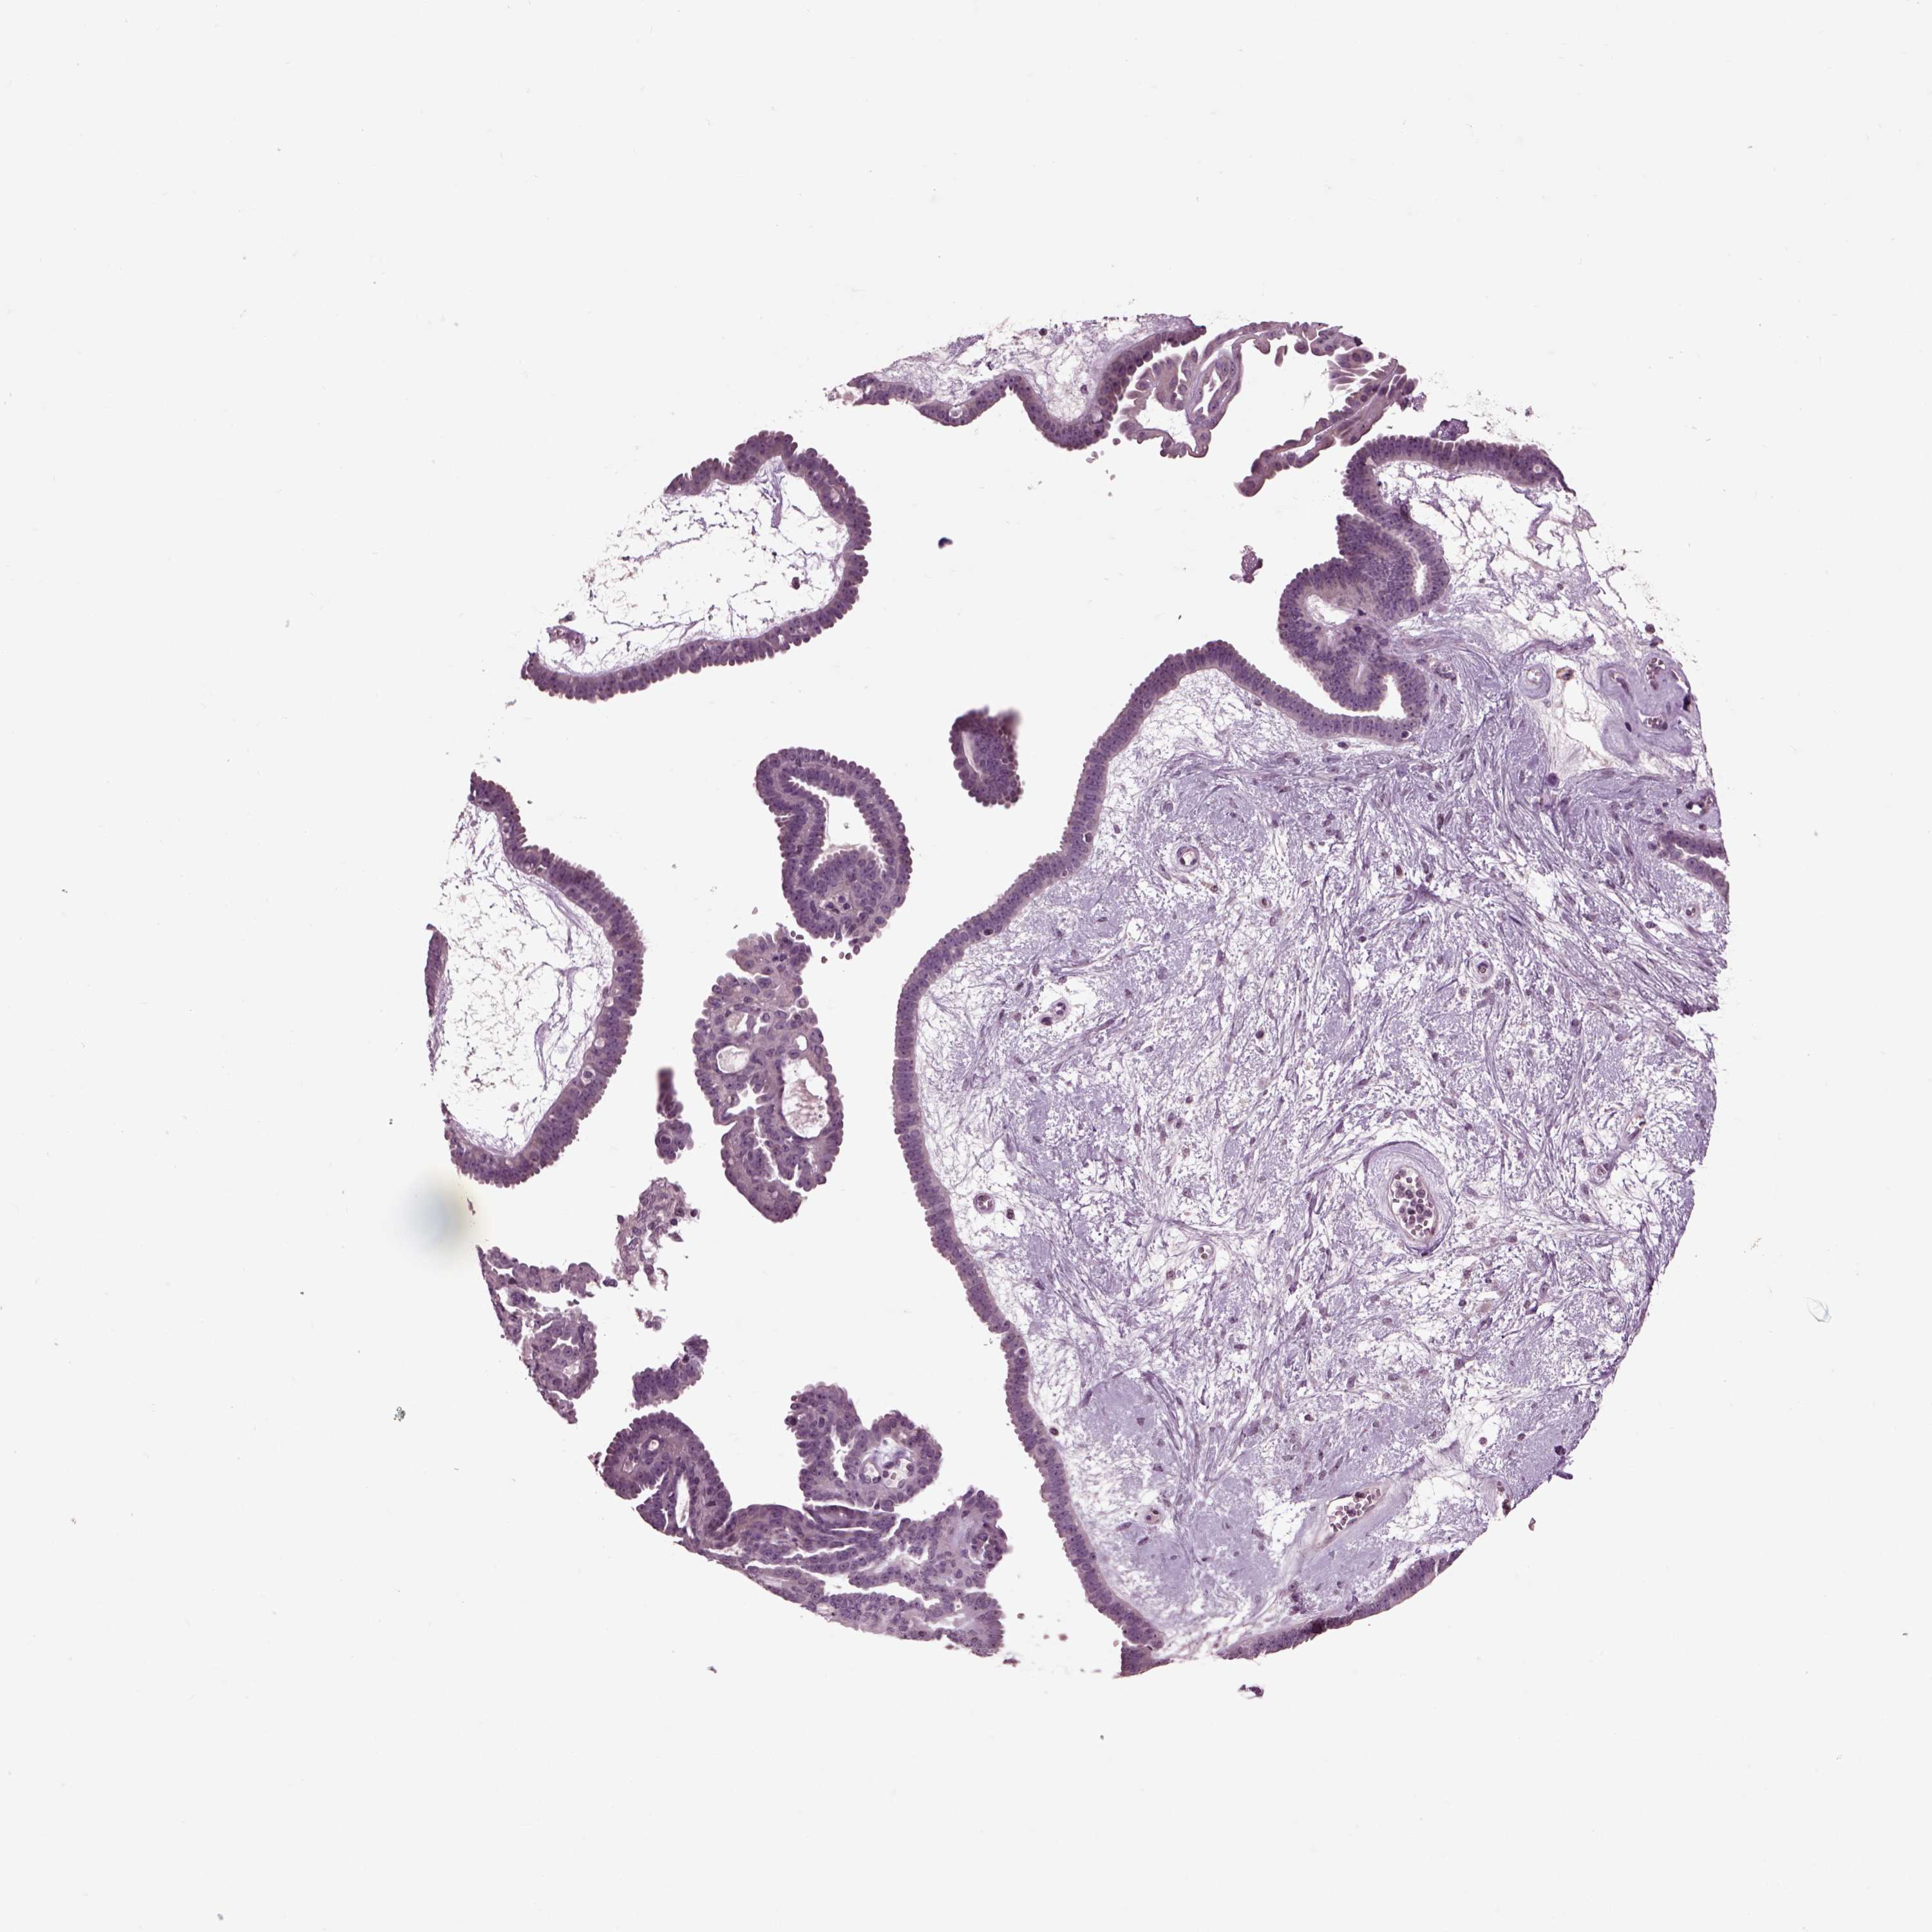

OVARIAN CANCER - Protein expressioni

A mouse-over function shows sample information and annotation data. Click on an image to view it in a full screen mode. Samples can be filtered based on level of antibody staining by selecting one or several of the following categories: high, medium, low and not detected. The assay and annotation is described here.

Note that samples used for immunohistochemistry by the Human Protein Atlas do not correspond to samples in the TCGA dataset.

Antibody stainingi

Antibody staining in the annotated cell types in the current human tissue is reported as not detected, low, medium, or high, based on conventional immunohistochemistry profiling in selected tissues. This score is based on the combination of the staining intensity and fraction of stained cells.

Each image is clickable and will lead to virtual microscopy that enables deeper exploration of all samples and also displays staining intensity scores, fraction scores and subcellular localization as well as patient and tissue information for each sample.

Antibody HPA008759

Antibody HPA012602

Antibody CAB009403

Cystadenocarcinoma, serous, NOS

Cystadenocarcinoma, mucinous, NOS

Carcinoma, endometroid